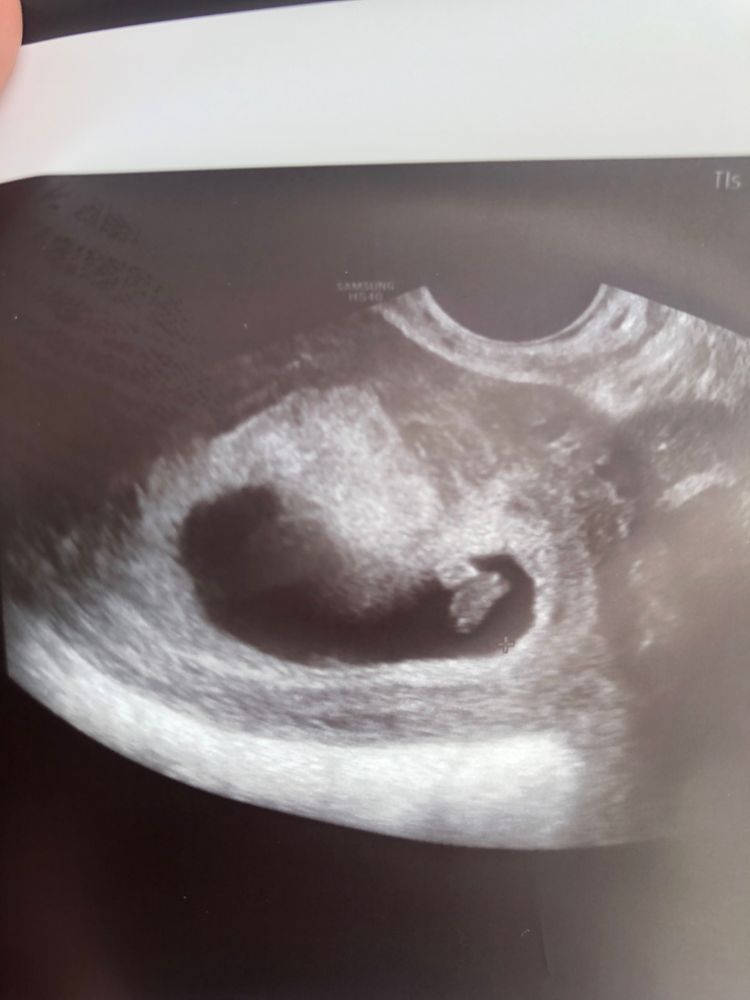

Узи в 7нед+4

bravo gun, сходила, только что написала пост) Что-то мне там узист намерила, я только разобрала, что КТР 6,3 мм сердцебиение 125-135. В заключении написали маточная беременность 6 недель. Врач моя после УЗИ сказала, что это норма для моего срока, и вероятнее всего была поздняя овуляция, так что я выдохнула)

Сердцебиение ниже нормы, у меня было 167

JT, сердцебиение соответствует сроку беременности, посмотрите любые таблицы и не вводите в заблуждение автора. Сердцебиение в 7 недель ориентировочно 125-140 уд/мин

Marie, у нее почти 8 недель, там от 149, я ходила на точно таком же сроке и мне писали нормы в узи